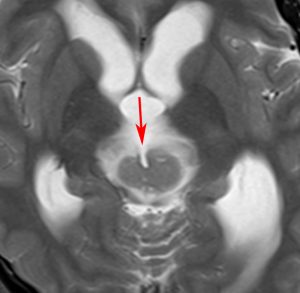

再発ジャーミノーマの画像です。延髄背側の閂 ovexという部位に再発しています。

このパターンはとても多いです。なぜかというと,全脳室照射の時に,第4脳室下端のovexの上衣 ependyum を照射野に入れない放射線治療医の先生がいるからです。放射線科の先生にもちょっとした知識が必要なのです。

これは再治療で腫瘍が消えても不可逆的な重症の延髄障害を残してしまいます。